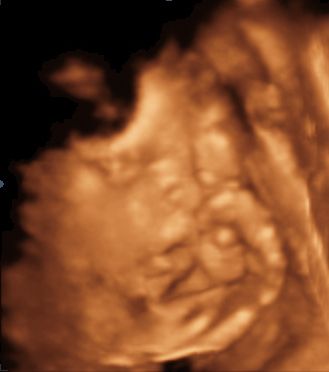

Svadobný album